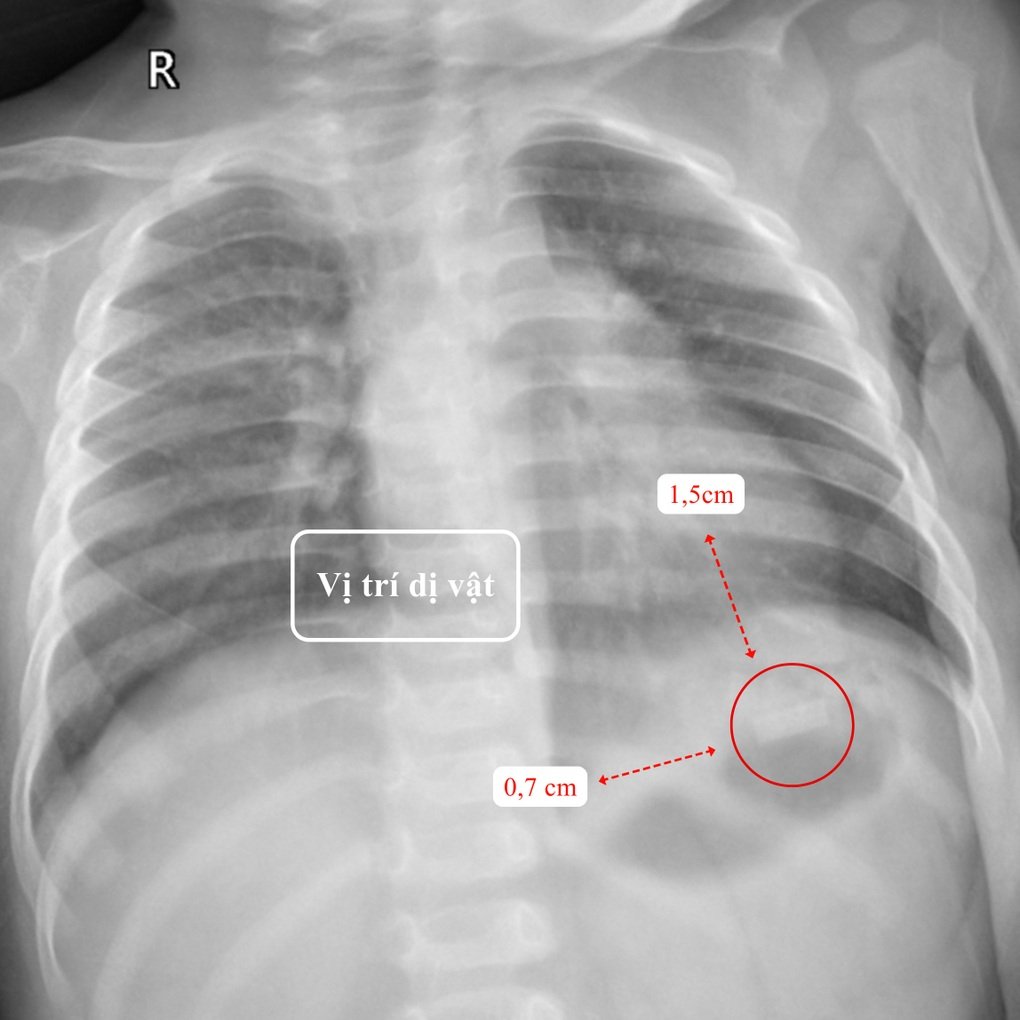

Di Jabatan Pediatrik - Hong Ngoc - Hospital Besar Phuc Truong Minh, hasil pemeriksaan klinikal dan paraklinikal menunjukkan bendasing logam berbentuk segi empat tepat berukuran 1.5x0.7cm, dengan sudut tajam, nipis dan tajam seperti bilah pisau yang terletak di hipokondrium kiri, kedudukan belon perut bayi T. Selain itu, akibat tertelan bahagian dadah yang beracun, keletihan dan bibir pucat.

Lokasi objek asing pada filem X-ray (Foto: BVCC).